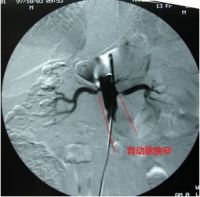

1.血管造影:是确诊肾动脉狭窄的唯一方法。不同病因的狭窄,造影表现可有一定差异。

动脉粥样硬化性狭窄:狭窄多位于肾动脉起始部或近端1/3。粥样斑块狭窄多呈偏心性,较大斑块突入管腔可表现为充盈缺损,狭窄段后可出现梭形扩张。腹主动脉常同时可见迂曲、延长、扩张及狭窄等动脉硬化的表现。

多发性大动脉炎:狭窄多位于肾动脉起始段,狭窄段光滑呈管状,常伴有狭窄后扩张,腹主动脉、骼总动脉或胸主动脉同时有狭窄与扩张相间,甚至动脉瘤扩张表现。